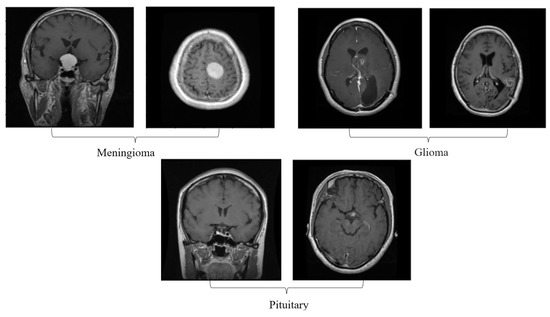

One of the crucial tasks in medical image processing is segmenting a brain tumor. Early diagnosis of brain tumors is thought to play a crucial role in improving treatment prospects and increasing patient survival rates. The most popular technique for diagnosing tumors is magnetic resonance imaging (MRI). Additionally, since contrast-enhanced MRI provides precise information about the tumors, current research aims to enhance the MRI diagnosis by including contrast agents. Images from computed tomography (CT) also show the internal structure of organs. The involvement of radiotherapists and their expertise is necessary for the manual segmentation of tumors. Due to the vast amount of MRI (magnetic resonance imaging) data, it might result in some errors. It is a demanding and challenging task. The conditions for automatic brain tumor segmentation were thus created. Currently, machine learning methods are crucial for analyzing medical imaging [1]. An unnatural cell growth inside the skull is a brain tumor. A malignant brain tumor, which is the most dangerous type of cancer, has immediate side effects, such as decreased life expectancy and cognitive decline. Magnetic resonance imaging (MRI) analysis is a common method for finding brain tumors. In this study, we employed these images to train our novel hybrid paradigm, which combines a convolutional neural network and a neural autoregressive distribution estimation [2]. Implementing interactive computational systems is the main goal of human–computer interaction (HCI) and related technologies. The studies in HCI place a strong emphasis on the use of systems, the development of novel methods that support user activities, information access, and seamless communication. Many different domains have made extensive use of AI and deep-learning-based models, producing cutting-edge outcomes. In the current study, a model for gesture recognition relevant to the HCI domain was implemented using convolutional neural networks based on a crow search [3]. In IoT-based healthcare systems, the classification of brain tumors (BT) is crucial for the diagnosis of brain cancer (BC). The most common application of artificial intelligence (AI) methods based on computer-aided diagnostic systems (CADS) is the precise detection of brain cancer. However, because artificial diagnostic systems are inaccurate, healthcare providers are not effectively utilizing them in the diagnosis of brain cancer. In this study, we proposed a robust deep learning (DL) brain tumor classification method to address the issue of accuracy in current artificial diagnosis systems [4]. In today’s health system, clinical diagnosis has taken on a significant role. Brain cancer, which is the most serious illness and the main cause of death worldwide, is a significant area of study in the field of medical imaging. A rapid and accurate diagnosis based on magnetic resonance imaging can enhance the examination and prognosis of brain tumors. Medical imagery must be recognized, segmented, and classified in order for computer-aided diagnosis methods to assist radiologists in the accurate detection of brain tumors [5]. All aspects of human life have been impacted by technological advancements. For instance, technology’s use in medicine has significantly benefited human society. This study focused on using technology to help treat brain tumors, one of the most common and deadly diseases ever. According to a “brain tumor” website estimate, about 700,000 Americans have primary brain tumors, and each year another 85,000 people are added to this estimate. As a result, many people pass away each year. Artificial intelligence has helped humans and medicine to find a solution to this issue. The most common technique for diagnosing brain tumors is magnetic resonance imaging (MRI) [6]. Transfer learning is the name given to machine learning methods that concentrate on learning from similar tasks in order to enhance generalization in the tasks of interest. Transfer learning is crucial for developing strategies in magnetic resonance imaging (MRI) that address the variations in MR images from various imaging protocols or scanners. In addition, machine learning models that were trained to solve various tasks related to the task of interest can be used again thanks to transfer learning [7]. Researchers are required to automate brain tumor detection and diagnosis due to a sharp rise in cases. Due to the various characteristics of tumors, the classification of multiple tumors in brain images is a current research topic. Deep neural networks are now frequently used to help neurologists classify medical images. The drawbacks of deep networks include overfitting and the disappearing gradient problem [8]. The field of artificial intelligence is rapidly developing, with new opportunities in diagnostic radiology being made possible by contemporary technological advancements and the expansion of electronic health data. In the past few years, deep learning (DL) algorithms consistently got better at a wide range of medical image tasks. On non-contrast computed tomography (NCCT) of the head, DL algorithms were suggested as a tool to identify different types of intracranial hemorrhage. The capacity for DL algorithm image interpretation support might enhance the diagnostic yield of CT for identifying this urgent condition in subtle, acute cases, potentially accelerating treatment when necessary, and improving patient outcomes [9]. Because of the complexity and importance of brain tumor segmentation in the medical context, numerous automated and semi-automated segmentation processes were developed. To identify a typical medical imaging dataset, the majority of these algorithms were tested on fewer metrics with varying parameters. The various types of brain tumors shown in Figure 1 were classified according to their stage: meningioma, glioma, and pituitary [10]. A specific type of brain tumor known as a glioma can develop in a different location and have a different appearance and size. Compared with a low-grade glioma, a high-grade glioma (HGG) is a serious form of cancer (LGG). These tumors necessitate manual diagnosis, which takes time and effort. As a result, in clinical settings, MRI is helpful to evaluate gliomas because it offers crucial information about tumor regions. In this study, a feature selection method based on active deep learning was proposed to segment and identify brain tumors [11]. A deep neural network-based 3D-CNN with 3D random aspirants as a fully connected layer (FCL) was used for brain tumor segmentation, which is essential for reducing false positive (FP) rates [12].

Figure 1.

Different kinds of brain tumors based on their stage: meningioma, glioma, and pituitary.